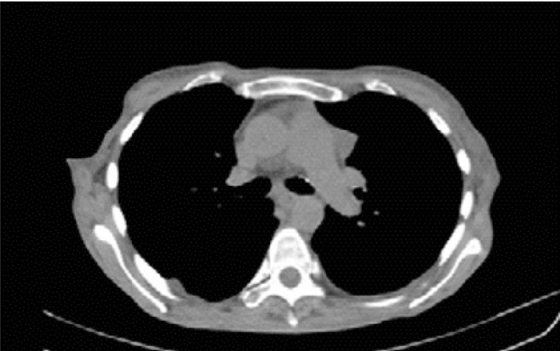

La paciente fue enviada 5 meses después a gastroenterología para descartar cáncer gástrico. Como parte del protocolo prequirúrgico para la realización de endoscopia se observó ensanchamiento mediastinal en la telerradiografía de tórax (Figura 1). El reporte histopatológico de la biopsia de estómago fue atrofia, engrosamiento de la capa muscular e infiltrado linfoplasmocitario, sin cambios compatibles con cáncer. En la tomografía toracoabdominal (Figura 2) se confirmó la tumoración en mediastino anterior. Fue sometida a toracotomía, donde se identificó un tumor mediastinal anterior de 8 a 10 cm, clasificado como timoma B1, con invasión a pericardio parietal y rama pulmonar izquierda.